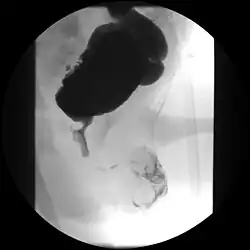

Die Diagnose wird aufgrund der charakteristischen Wandverdickung mit Unregelmäßigkeiten im Ultraschall gestellt und mittels Miktionszystourethrogramm bestätigt.